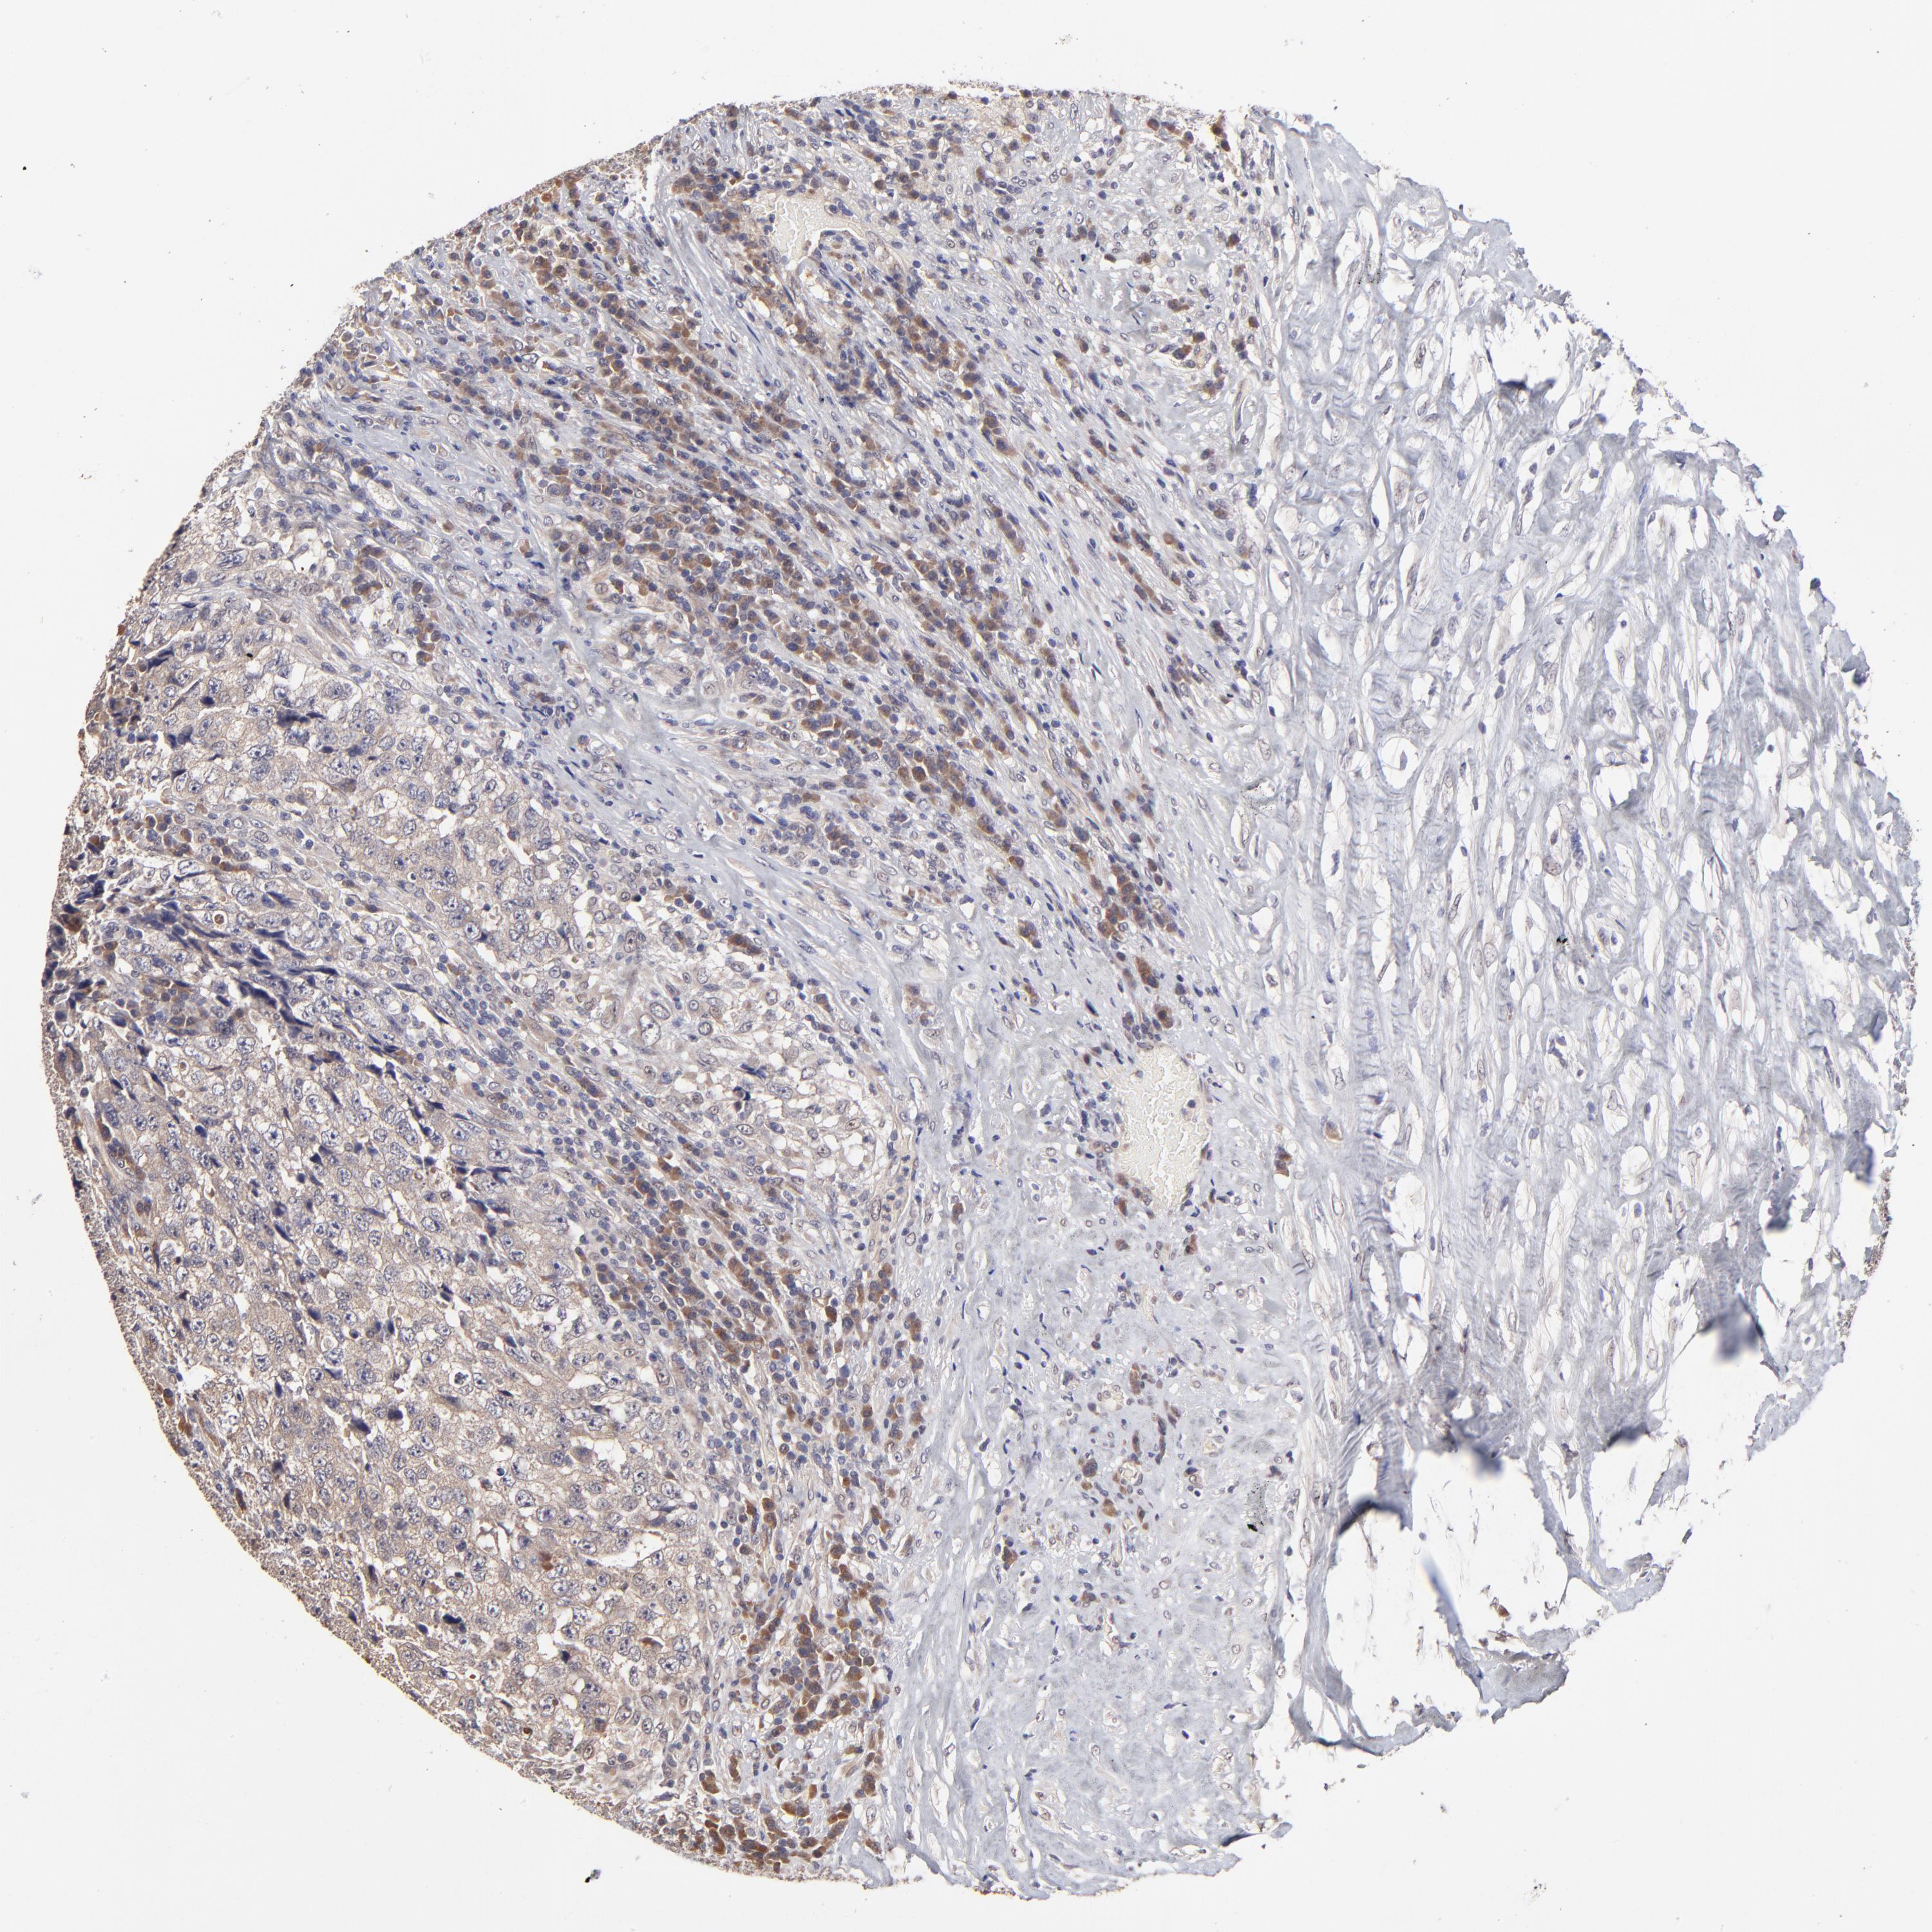

TESTIS CANCER - Protein expressioni

A mouse-over function shows sample information and annotation data. Click on an image to view it in a full screen mode. Samples can be filtered based on level of antibody staining by selecting one or several of the following categories: high, medium, low and not detected. The assay and annotation is described here.

Note that samples used for immunohistochemistry by the Human Protein Atlas do not correspond to samples in the TCGA dataset.

Antibody stainingi

Antibody staining in the annotated cell types in the current human tissue is reported as not detected, low, medium, or high, based on conventional immunohistochemistry profiling in selected tissues. This score is based on the combination of the staining intensity and fraction of stained cells.

Each image is clickable and will lead to virtual microscopy that enables deeper exploration of all samples and also displays staining intensity scores, fraction scores and subcellular localization as well as patient and tissue information for each sample.

Antibody HPA003204

Staining

High

Medium

Low

Not detected

Intensity

Strong

Moderate

Weak

Negative

Quantity

>75%

75%-25%

<25%

None

Location

Nuclear

Cytoplasmic/membranous

Cytoplasmic/membranous,nuclear

Carcinoma, Embryonal, NOS

Seminoma, NOS